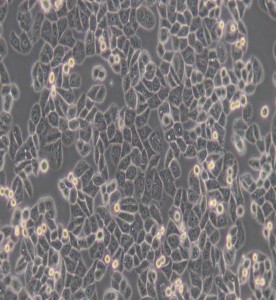

MDA-MB-468人乳腺癌細胞(DMEM)

中文名稱 :人乳腺癌細胞

細胞簡稱 : M DA-M B -468

細胞形態(tài) : 上皮細胞樣

生長特性 : 貼壁細胞

M DA-M B -468細胞是由C ailleauR等人于1977年從一位患有轉(zhuǎn)移性乳腺癌的51歲黑人女性的胸腔積液中分離得到的。雖然供體組織的G6PD 等位基因雜合,但M DA-M B -468細胞始終表現(xiàn)為G6PD A 表型。p53M DA-M B -468細胞是由C ailleauR等人于1977年從一位患有轉(zhuǎn)移性乳腺癌的51歲黑人女性的胸腔積液中分離得到的。雖然供體組織的G6PD 等位基因雜合,但M DA-M B -468細胞始終表現(xiàn)為G6PD A表型。p53基因273位密碼子存在G →A 突變,從而導(dǎo)致A rg→His替代。每個M DA-M B -468細胞上存在1×10^ 6個EG F受體。